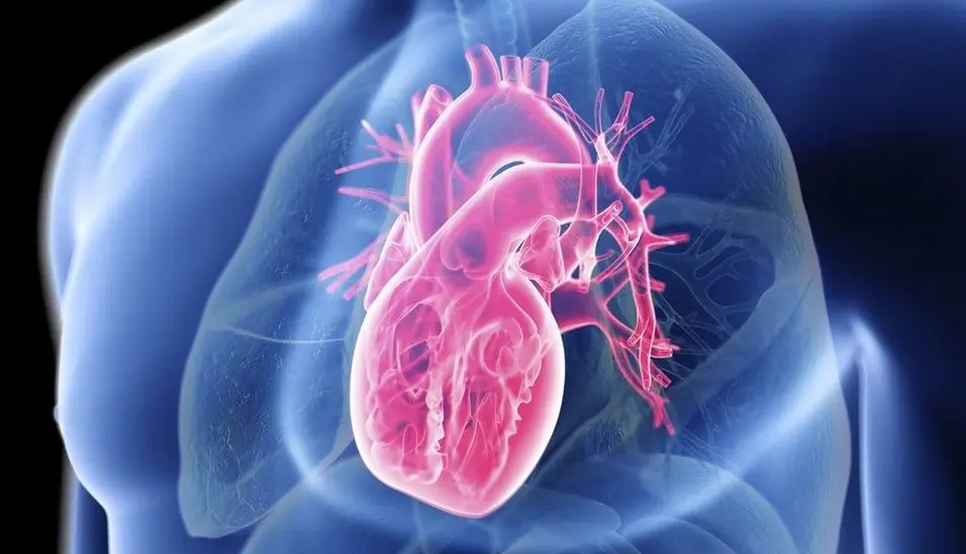

शुक्लागण्डकी नगरपालिका–५ बेलचौतारास्थित जिपी कोइराला श्वासप्रश्वास उपचार केन्द्रमा बिहीबार आयोजित निःशुल्क मुटुरोग परीक्षण तथा उपचार शिविरबाट ७८० जना लाभान्वित भएका छन् । केन्द्रको आयोजना तथा सहिद गङ्गालाल राष्ट्रिय हृदयरोग केन्द्रको प्राविधिक सहयोगमा सञ्चालित शिविरमा निःशुल्क इसिजी सेवा, भिडियो एक्सरे सेवा, मधुमेह परीक्षण गरिएको थियो । हृदयरोग केन्द्रका ११ जनाको स्वास्थ्यकर्मी टोलीलाई जिपी कोइराला श्वासप्रश्वास उपचार केन्द्रका चिकित्सकले सघाएका थिए । जटिल समस्या भएका बिरामीलाई थप उपचारका निम्ति हृदय केन्द्रमा जान सुझाव दिइएको थियो ।